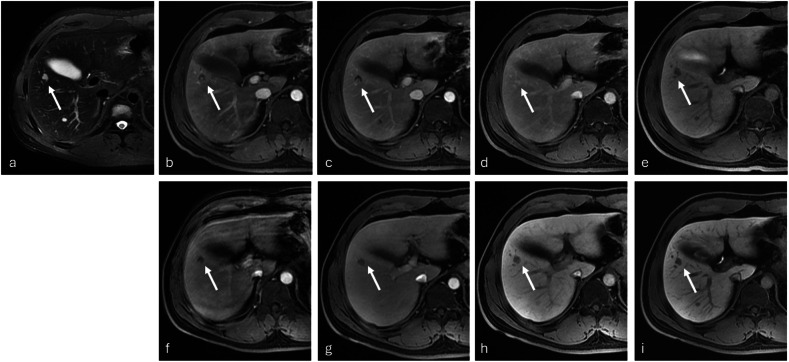

Abstract Image